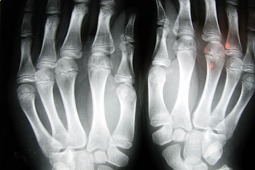

W Polsce na osteoporozę może chorować około 3 mln osób powyżej 65. roku życia. W całej Europie, Japonii i USA liczbę pacjentów z osteoporozą szacuje się na 75 mln. Największym problemem nie jest jednak sama osteoporoza, lecz złamania, do których ta choroba nieuchronnie prowadzi przy braku odpowiedniej profilaktyki i leczenia.

Osteoporoza występuje w Polsce u 30 proc. kobiet i 8 proc. mężczyzn po 50. roku życia. Szacuje się, iż z powodu osteoporozy w Europie co 30 sekund dochodzi do złamania.